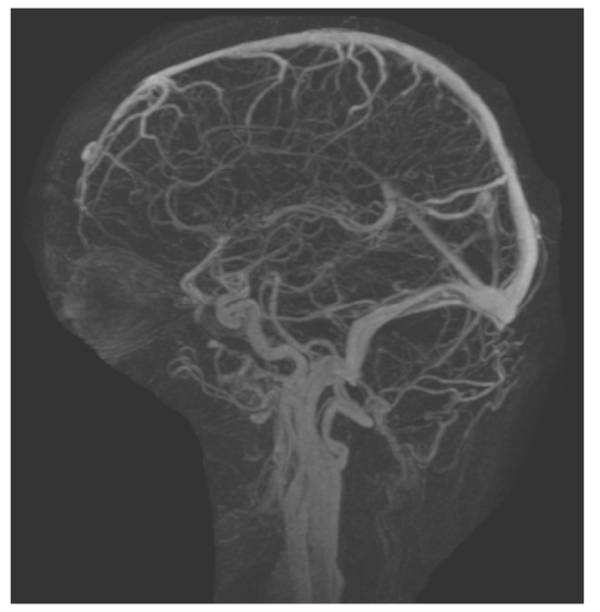

This case includes a 39-year-old woman with class 1 obesity and polycystic ovarian syndrome (PCOS), which significantly exacerbated her hair loss. She also had a history of idiopathic intracranial hypertension (IIH) that was diagnosed at 14 years of age and treated with steroids and diuretics. The treatment has been discontinued since 13 years. The patient’s medications included levothyroxine (100 µg daily) for hypothyroidism and atorvastatin (10 mg) for hypercholesterolemia. She visited the dermatology clinic complaining of hair loss since 1 year, and was diagnosed with Ludwig stage 1 female pattern hair loss. Daily topical solution of minoxidil and oral solution of spironolactone (50 mg) were prescribed. After 3 months, the patient reported new facial hair growth. No adverse effects were observed; thus, spironolactone dose was increased to 100 mg daily. Two months later, the patient presented at the neurology clinic due to visual obscuration, blurred vision, dizziness, pulsating tinnitus, and headache. These complaints were observed since the beginning of the treatment and were mild, but then progressively worsened with treatment maintained up until presentation at the neurology clinic. The initial impression was recurrence of IIH and the patient was advised for further evaluation. She refused to undergo lumbar puncture. Magnetic resonance imaging (Fig. 1) and magnetic resonance venography (Fig. 2) were performed, and acetazolamide (250 mg) was prescribed. Ophthalmologic examination revealed an optic nerve head showing clear temporal margins and evidence of old blurring of the superionasal margins. Venous pulsation was evident; there were no overt signs of acute papilledema. The final impression was recurrence of bilateral papilledema. The patient continued to complain of dizziness, frontal headache, which was throbbing in character, and associated with occasional nausea. She also reported a weight gain of 6 kg in 1 week, without any changes in diet and exercise. Spironolactone administration was discontinued, but minoxidil application was continued. After six weeks, all the symptoms were significantly improved. Then, acetazolamide administration was also discontinued. There were no electrolyte disturbances or blood pressure abnormalities detected throughout the spironolactone treatment.